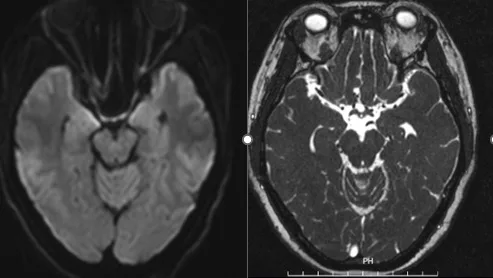

Hình ảnh kết quả chụp cộng hưởng từ của người bệnh

Dựa trên các kết quả dịch não tủy, máu, CHT sọ não, CHT cổ, kết quả tự kháng thể… các bác sĩ đã hội chẩn và đưa ra chẩn đoán Liệt dây IV trung ương căn nguyên do viêm và đã áp dụng phác đồ: corticoid liều cao, vitamin nhóm B, tăng dẫn truyền thần kinh, dinh dưỡng thần kinh. Sau 2 tuần điều trị vận động nhãn cầu về các phía đã đạt tối đa như mắt trái, khám vận động 2 mắt cân xứng, người bệnh hết các triệu chứng nhìn đôi, tự tin bỏ che mắt khi đi lại, lên xuống cầu thang bình thường, không còn cảnh nhìn món này lại gắp phải món khác. Người bệnh được ra viện dùng thuốc theo đơn ngoại trú trong niềm hạnh phúc của gia đình.